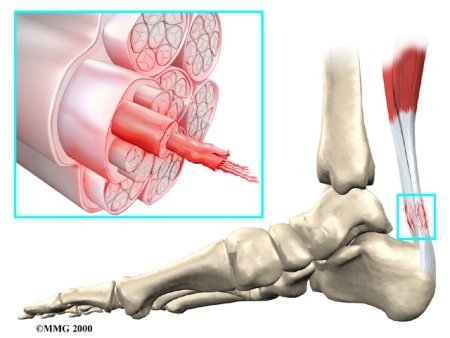

Inflammation can develop in any tendon in the body. Tendons are fibrous structures—made up of mostly collagen fibers—that connect muscle tissue to bone. Collagen is a structural protein that is the key building block of many structures in the body. Collagen helps form robust connective tissue by creating a network of collagen fibers that twist around one another in a manner that is similar to the strands of a nylon rope.

In addition to being made up primarily of collagen, the tendon is surrounded by a protective lining called a tendon sheath. The tendon sheath is filled with a lubricating fluid that helps tendons move easily against surrounding tissue. If the tendon sheath becomes inflamed, it can lead to an issue called tenosynovitis. Both the tendon and its sheath may also become inflamed at the same time.